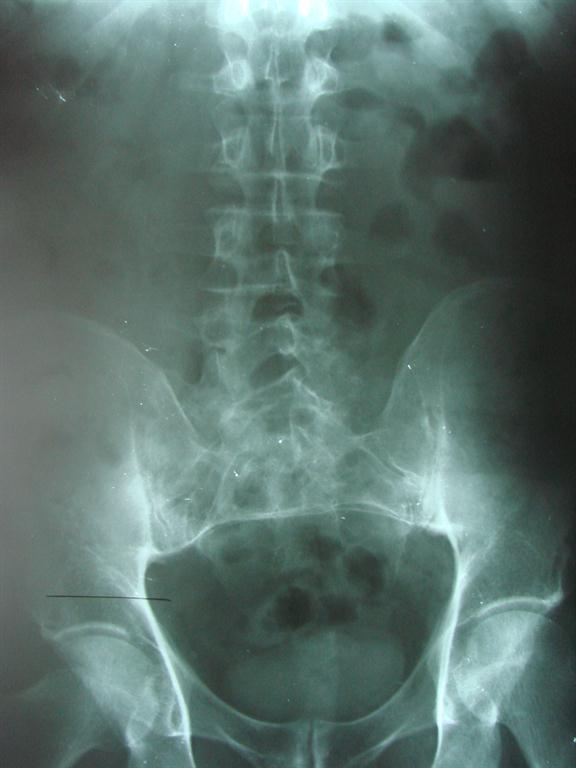

A short leg can be due to a variety of situations that the doctor may address first before addressing your short leg. We at Aurora Chiropractic Center will determine if the short leg is truly due to structure. If it is, you will likely be fitted with a heel lift to correct the inequality. If the inequality is larger, you may need to add a little at a time to allow your spine to adjust. In addition to correcting the difference, your chiropractic physician will align your spine with spinal manipulation.

A thorough, clinical examination that may include imaging is important to your short leg diagnosis and management.